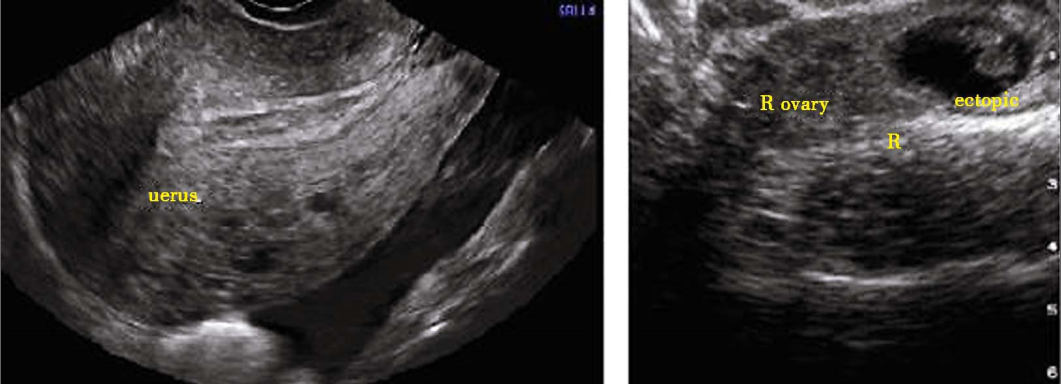

1.超声检查 超声检査对异位妊娠诊断必不可少,还有助于明确异位妊娠部位和大小,经阴道超声检查较经腹部超声检查准确性高。异位妊娠的声像特点:宫腔内未探及妊娠囊。若宫旁探及异常低回声区,且见卵黄囊、胚芽及原始心管博动,可确诊异位妊娠;若宫旁探及混合回声区,子宫直肠窝有游离暗区,虽未见胚芽及胎心搏动,也应高度怀疑异位妊娠;即使宫外未探及异常回声,也不能排除异位妊娠。由于子宫内有时可见到假妊娠囊(蜕膜管型与血液形成),应注意鉴别,以免误诊为宫内妊娠。子宫直肠窝积液也不能诊断异位妊娠。超声检查与血hCC测定相结合,对异位妊娠的诊断帮助更大。

异位妊娠超声表现